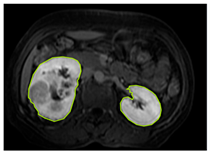

3.2.1. ROI Dataset

The images used in the study include different anatomical areas, such as the liver, spleen, and intestine. However, in order to process the data more quickly and provide more accurate results from the analysis, only the kidney areas (Regions of Interest, ROI) were extracted and evaluated. The Roboflow platform was used for spatial matching and segmentation of the kidneys. Polygonal ROI regions were defined by applying the semantic segmentation method, and then the transformations performed were verified by the radiologist, increasing the reliability of the system. In our study, MRI phase images were acquired at a resolution of 512 × 512 and the renal region of interest (ROI) was segmented and resized to 224 × 224 for input into the DenseNet architecture. In a similar study, Alhussaini et al. utilized 512 × 512 CT images and processed tumor-containing ROIs for their analysis; however, segmented region details were not provided [23]. Another study aimed to differentiate ccRCC from oncocytoma by extracting ROIs from T2-weighted images (T2-WI), pre-contrast T1-weighted images (T1-WI), and post-contrast arterial and venous phases. Tumor regions segmented at 100 × 100 mm were subsequently resized for input into the AlexNet model [24]. Unlike these studies, our approach involves segmenting the entire kidney, rather than solely the tumor region, to enable the deep learning model to leverage structural information for the organ as a whole.

Table 2 shows sample images containing ROI areas for different phases.

Table 2.

ROI areas in different phases.